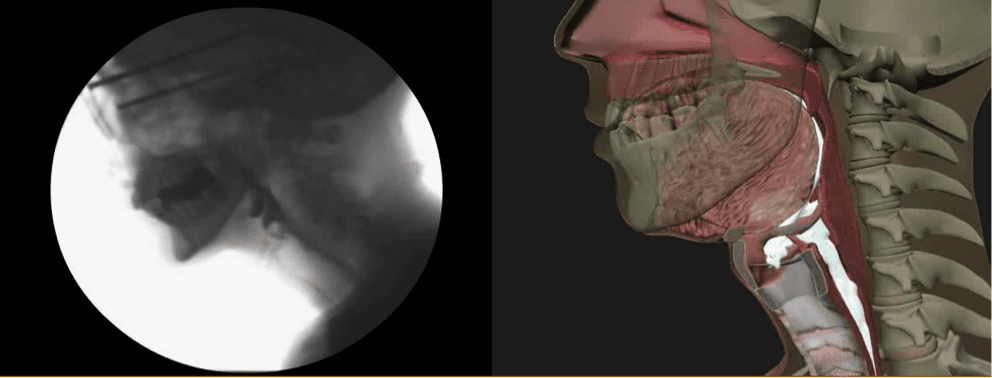

Video Swallow Study Example

Video Swallow Study Example. In elderly patients, difficulties with swallowing can cause anxiety around a meal, and panic associated with this activity of daily living can result in the individual socially isolating themselves. If there is a risk of aspiration (certain foods or liquids going into the airway)

The patient then is given a cup of thin liquid barium to drink freely and a masticated material coated with barium pudding (usually a cracker). Our video explains what happens in a videofluoroscopy swallow study. • how the food is swallowed.

The test is done to see: Like a video, these pictures are real time, live, moving images. A videofluoroscopic swallow study is considered the gold standard diagnostic tool for detecting dysphagia.

A Videofluoroscopic Swallowing Study Is An Instrumental Examination That Often Could Be A Good Option And A Very Useful Tool For The Swallowing Clinician.